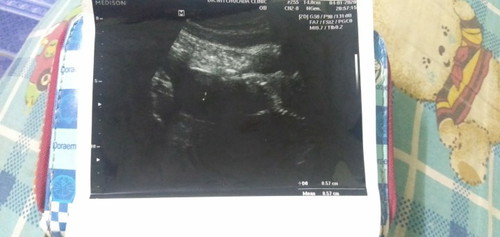

ตั้งครรภ์ได้1เดือน

ไปซาวมาเมื่อวันที่4หมอบอกว่ากำลังเปนตัวอ่อนมีสิทแท้งได้เพราะเรามีเลือดออกหมอให้ยามากินแร้วนัดอีกทีวันที่11นี้ รบกวนหน่อยน้ะค้ะพอดีเราพึ่งท้องแรกคะไม่ค่อยรุ้เท่ารัย